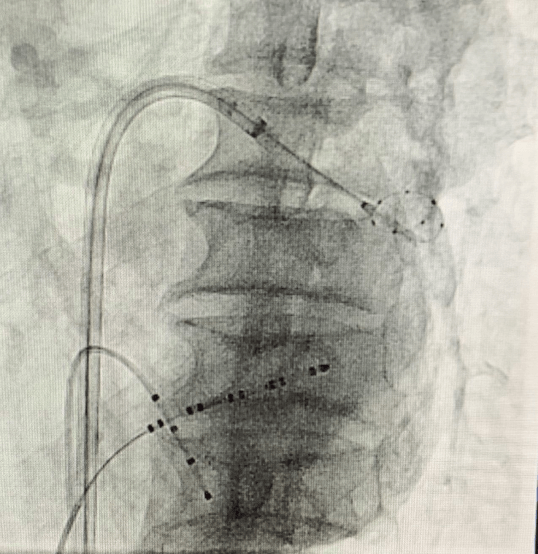

(手術過程)